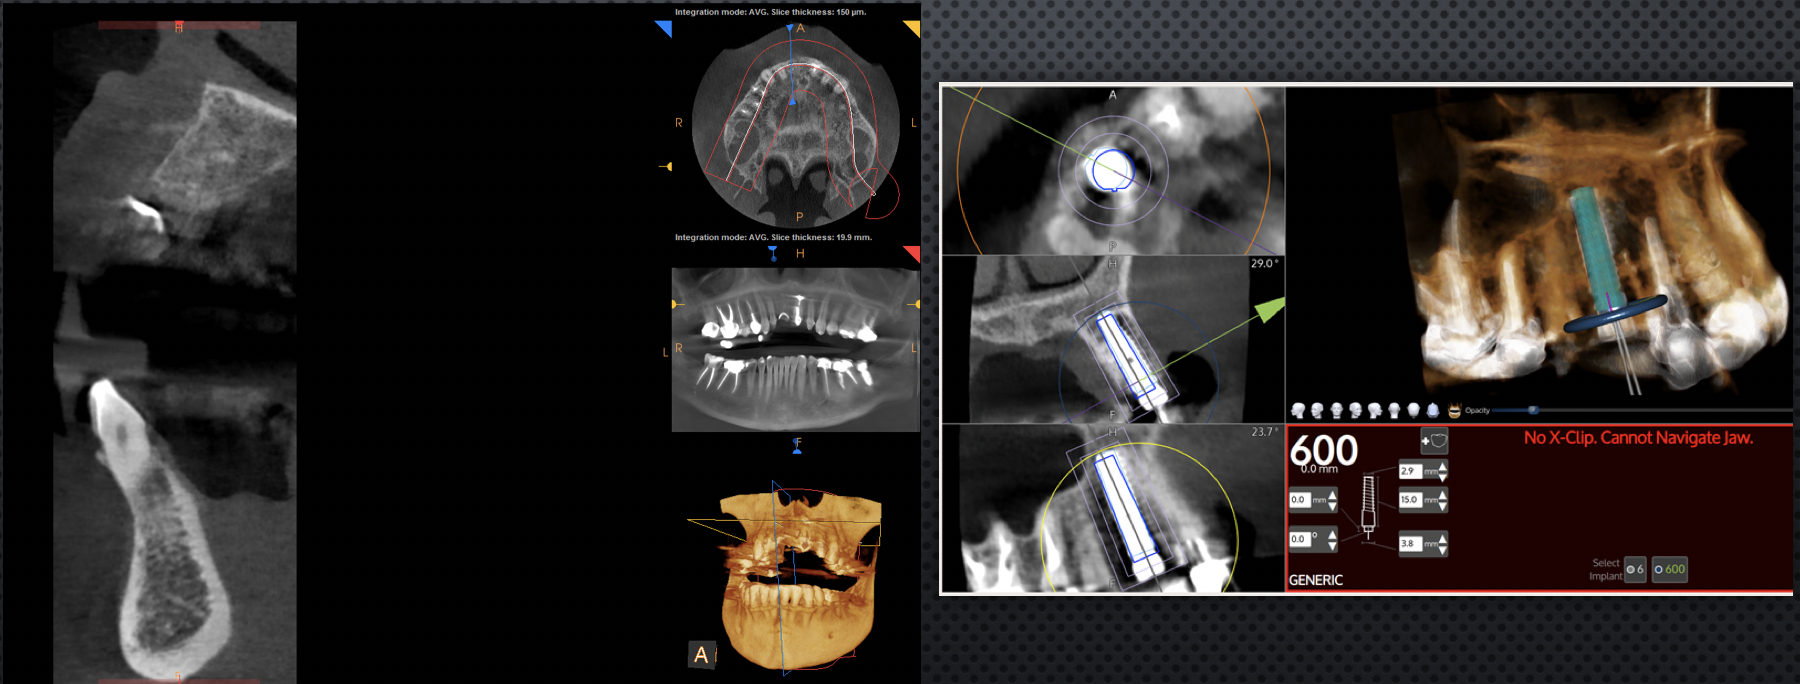

The next step that is possible with fully digital dentistry is dynamically navigated dental implants. Computer-assisted surgery can be either static or dynamic. Static guides are 3D printed from CAD/CAM and 3D data, as described in the previous section. Dynamic navigation combines digital data from CBCT scans and intraoral scanners so the surgeon can virtually plan the ideal implant location and then use that plan to surgically navigate the exact implant placement.

By using these three technologies together, the surgeon can plan and place implants with an optimal restorative goal in mind. Using dynamic navigation to more accurately place the implant can result in a more functional and esthetic outcome. Dynamic navigation tracks the patient position and live movements of the handpiece drill in real time on a computer screen. With dynamic guidance, the surgeon can view the handpiece's position, angle, and depth while drilling as they relate to the planned implant placement.

Clinical studies show that implants placed with dynamic navigation are more accurate than freehand implant placement.36 Static and dynamic image navigation are both highly accurate systems; however, dynamic systems have additional advantages. Patients can be scanned and planned and have surgery in one day, and plans can be altered during surgery as needed based on the clinical situation. Moreover, the entire field can be visualized throughout the process, allowing accuracy to be verified at any time.36

Fig 2. Left: Postsurgical evaluation of a bone graft in site No. 8 after extraction and graft. Right: Overlay of a CBCT after dynamically guided placement of an implant in site No. 6, showing the implant was ultimately placed where planned.

Figure 2